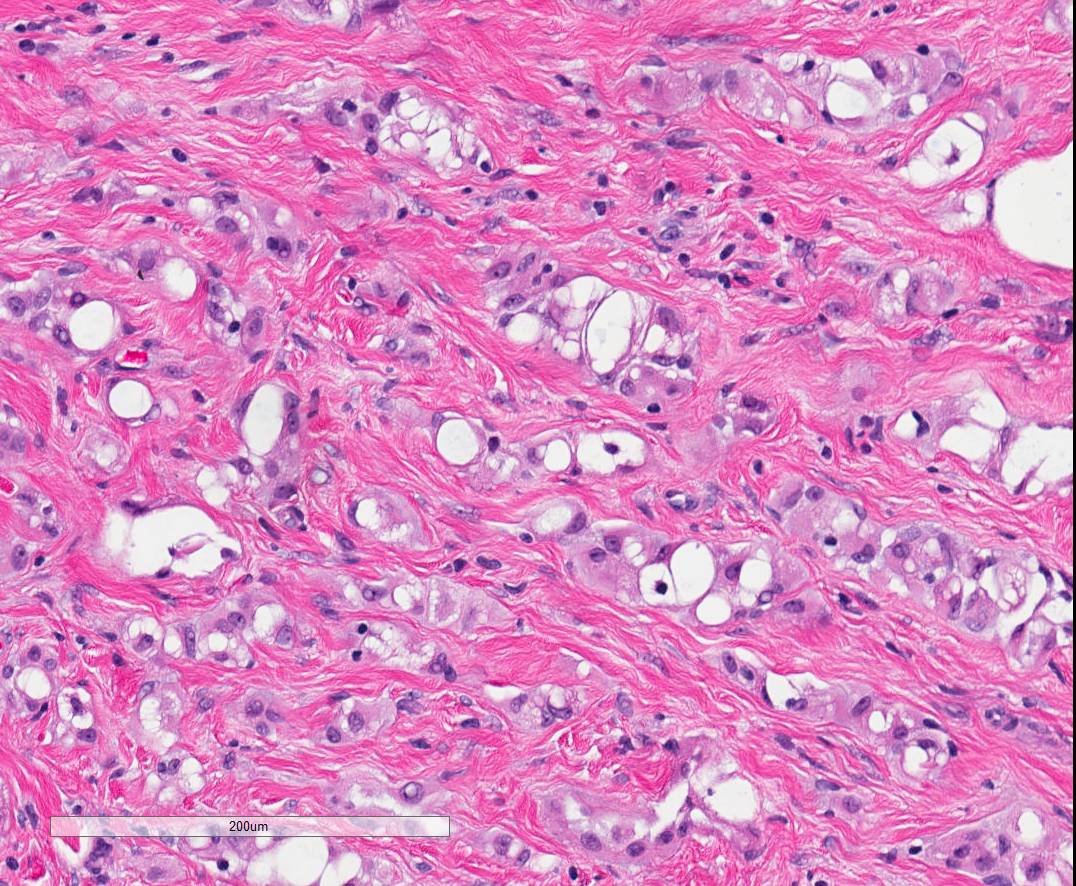

Angiosarcoma diagnostic difficulties Check out our new article ijp.iranpath.org/article_728541… Vidya Monappa